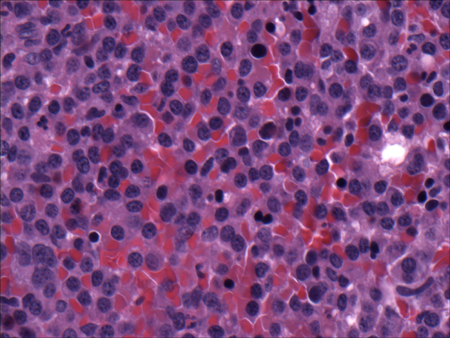

- biópsia renal:

os glomérulos demonstram tufos lobulares com matriz mesangial aumentada, proliferação de células endoteliais e membranas basais espessadas; depósitos mesangiais e subendoteliais